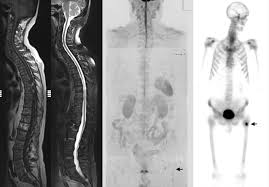

False Positive Diagnosis Of Disease Progression By Magnetic Resonance Imaging For Response Assessment In Prostate Cancer With Bone Metastases A Case Report And Review Of The Pitfalls Of Images In The Literature

False Positive Diagnosis Of Disease Progression By Magnetic Resonance Imaging For Response Assessment In Prostate Cancer With Bone Metastases A Case Report And Review Of The Pitfalls Of Images In The Literature from www.spandidos-publications.com